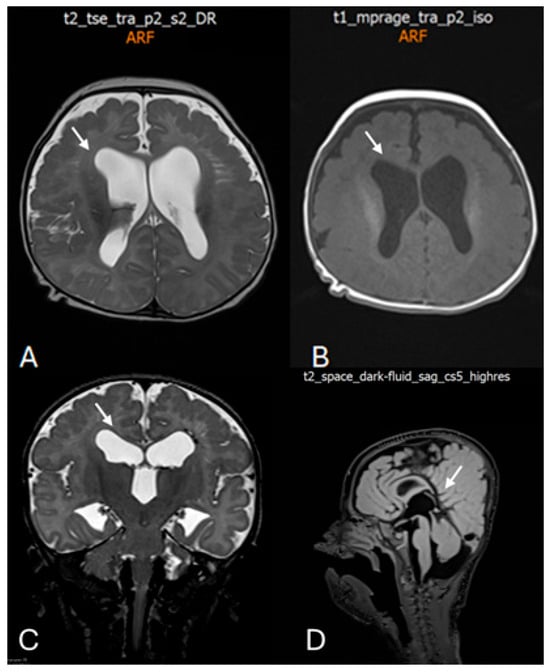

Background: Prenatal detection of fetal structural anomalies often prompts chromosomal analysis; however, chromosomal microarray analysis (CMA) has limited diagnostic yield for monogenic disorders. Whole-exome sequencing (WES) has emerged as a powerful tool for identifying single-gene etiologies, particularly in cases with complex neurodevelopmental phenotypes. Case Presentation: We report a female infant presenting with prenatally detected ventriculomegaly and inconclusive chromosomal testing. Prenatal investigations, including karyotyping and genome-wide chromosomal sequencing, identified several copy number variants classified as variants of uncertain significance but failed to establish a definitive diagnosis. Postnatally, the patient developed progressive neurological abnormalities, including microcephaly, facial dysmorphism, dystonic movements, and severe global developmental delay. Trio-based whole-exome sequencing identified a heterozygous de novo pathogenic missense variant in the DDX3X gene (c.976C>T; p.Arg326Cys), establishing the diagnosis of DDX3X-related neurodevelopmental disorder. Conclusions: This case highlights the diagnostic limitations of standard prenatal chromosomal testing in detecting monogenic neurodevelopmental disorders and underscores the critical role of timely genetic counseling and exome sequencing. Earlier selective implementation of WES during pregnancy could have enabled an earlier diagnosis, improved prognostic counseling, and optimized clinical decision-making. Full article

Show Figures

Figure 1